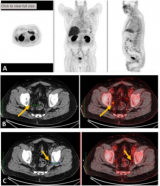

放射抗体偶联药物诱导PSMA阳性mCRPC患者的抗肿瘤活性

根据Ⅰ期ProstACT SELECT研究(NCT04786847) 的初步结果,首创的放射性抗体偶联药物TLX591(Lu-177 rosopatamab tetraxetan)在PSMA阳性转移性去势抵抗性前列腺癌(mCRPC)患者中显示出良好的疗效和安全性。1 2023-10-30 核技术放射诊疗靶向治疗